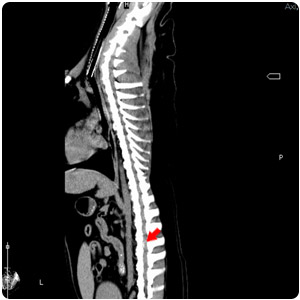

| 脊椎壓迫 transverse |

脊椎壓迫 sagittal |